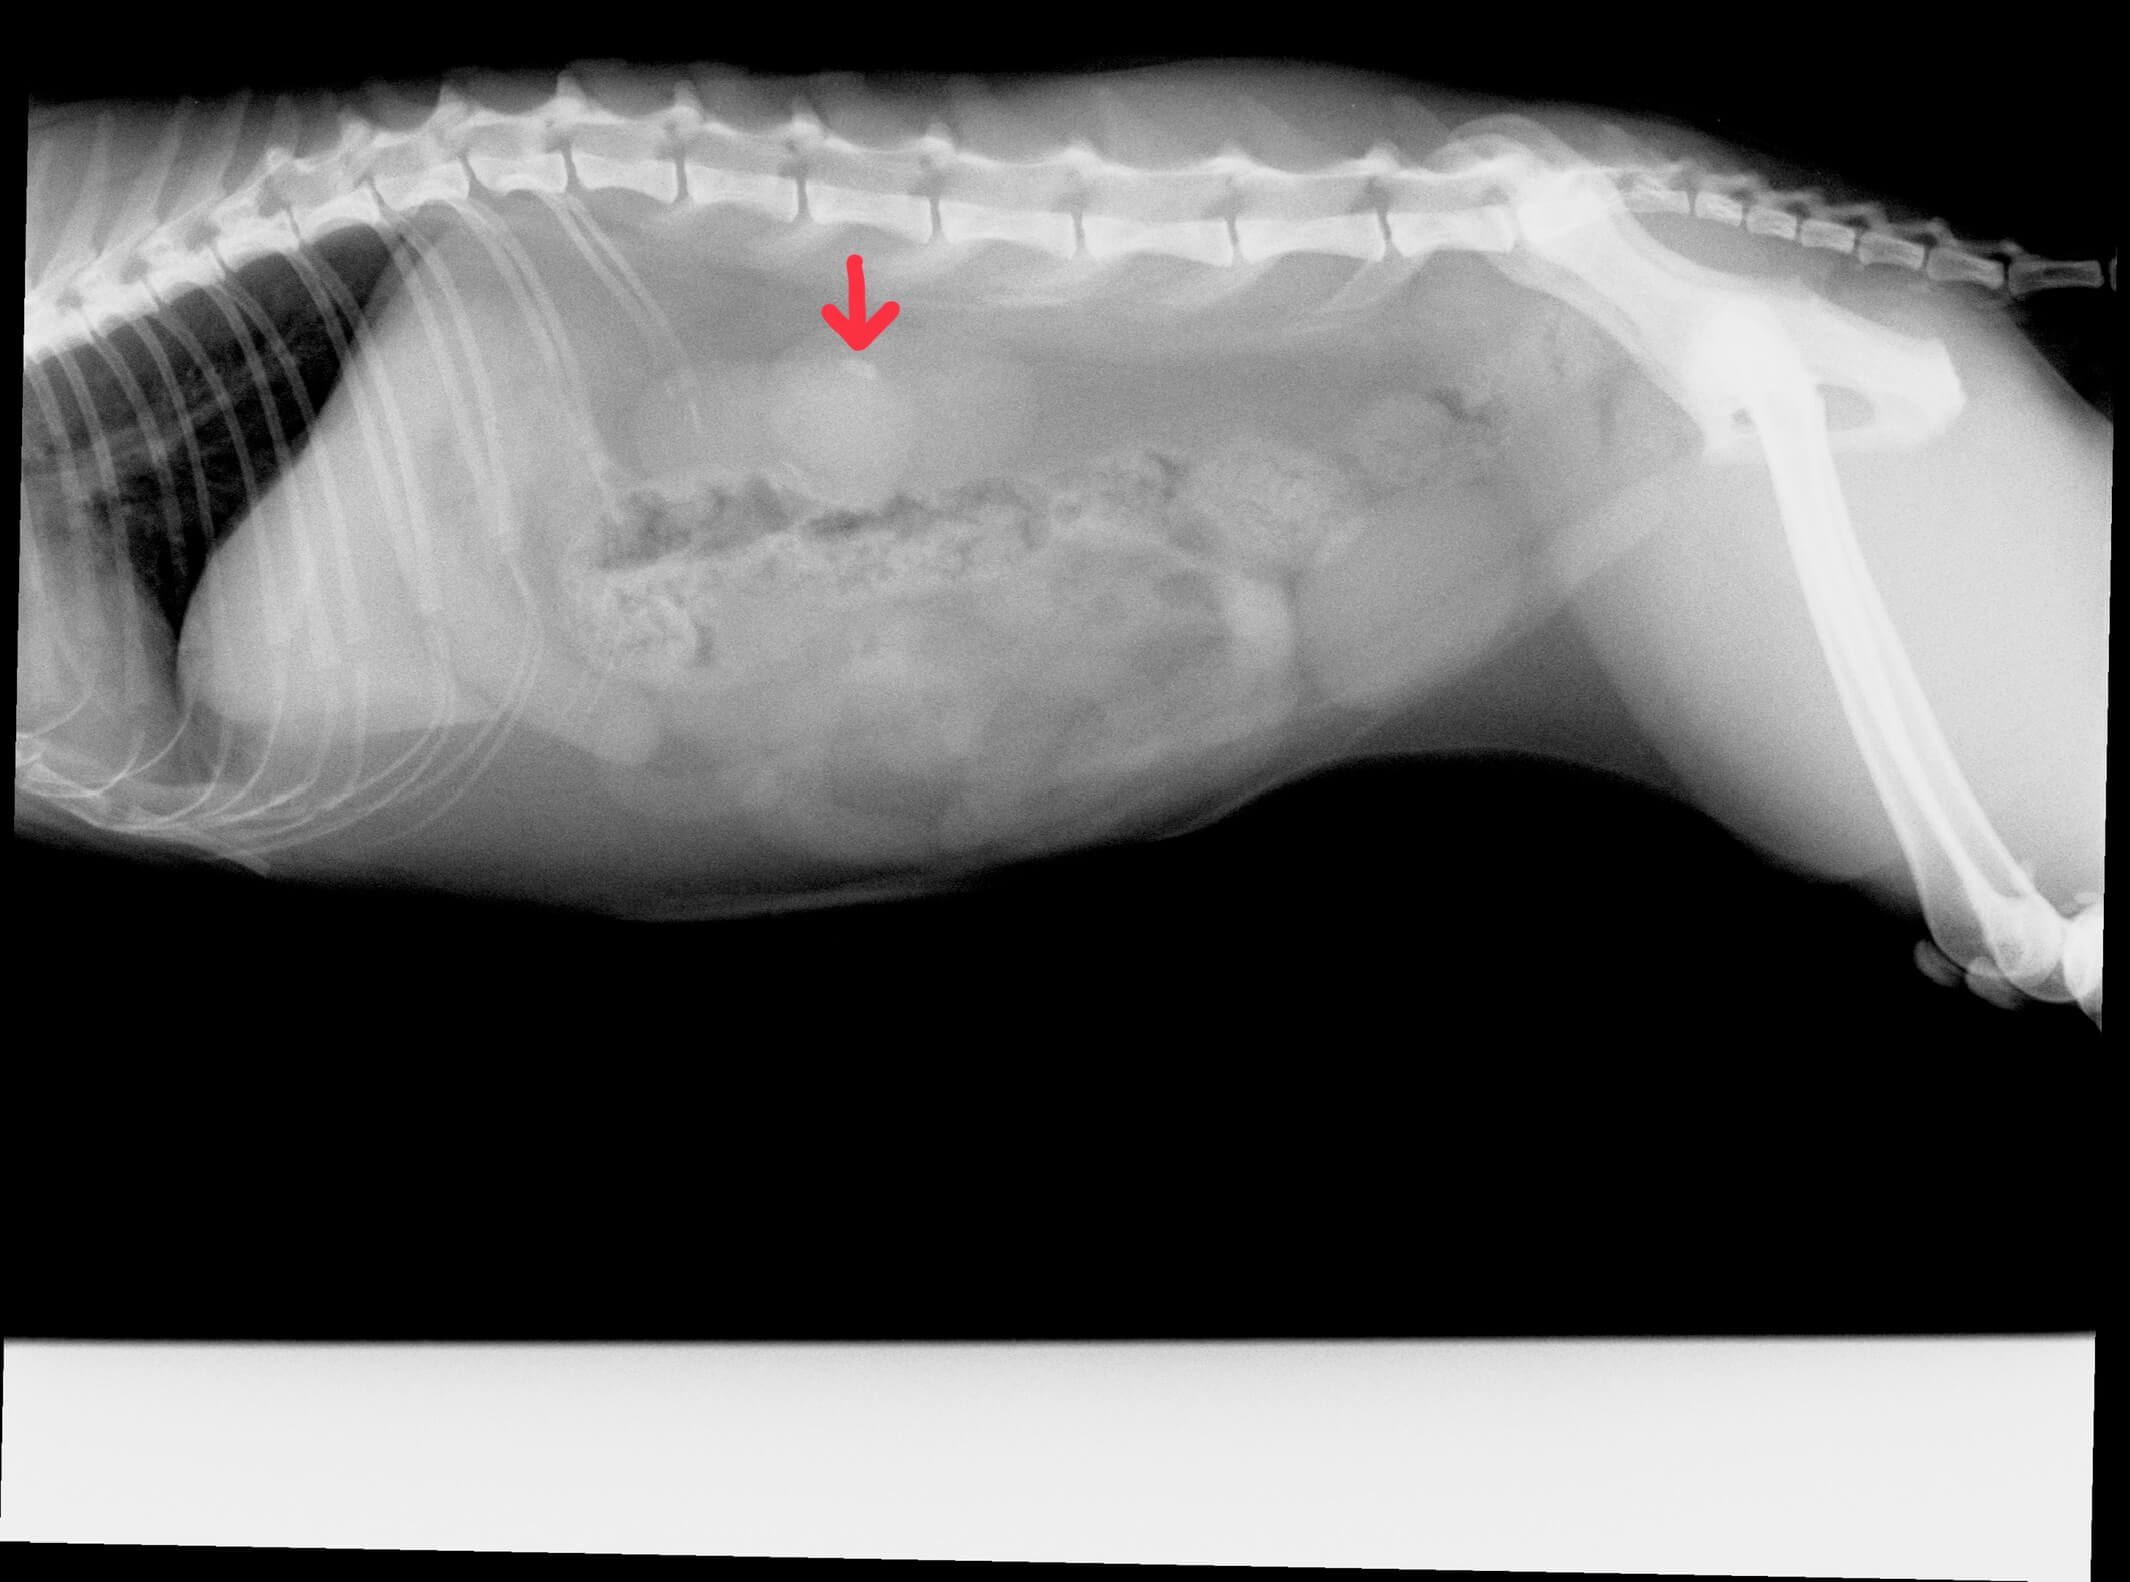

結石はレントゲン検査で白く見えます。 (矢印部)

手術後のレントゲン画像です。

手術前に見られた結石が消えています。 (矢印部)